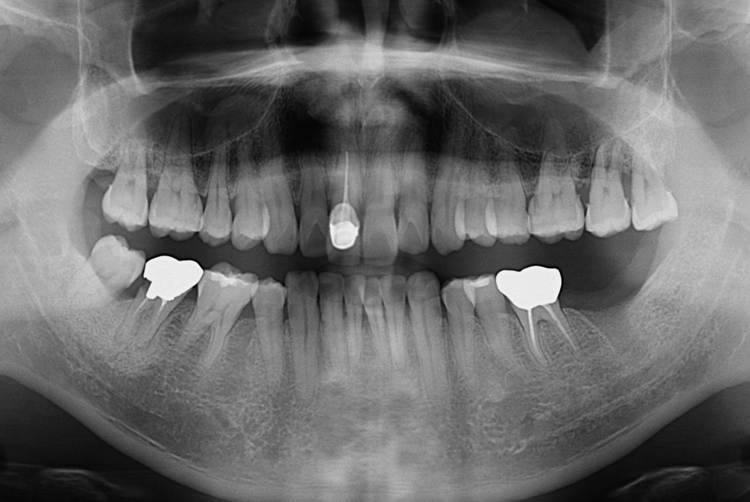

[임플란트] 어금니 임플란트

치료전 : 2017-06-21